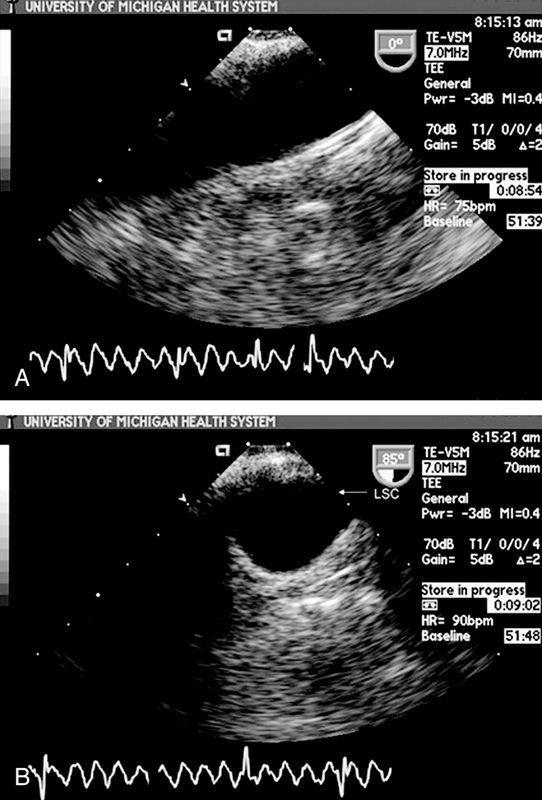

فحوصات تشخيصية لبعض امراض القلب والشرايين التاجية